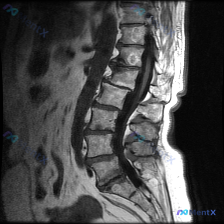

整理到一份影像资料,主诉考虑「脊柱侧弯」,但只放了一张矢状位腰椎MRI T1加权图像。 图像本身的客观表现大概是: - L1-L5椎体及骶骨轮廓清,高度大致正常,未见明显压缩骨折或滑脱 - 椎体骨髓信号中高,符合脂肪沉积,未见明确骨质破坏 - 椎间盘信号中等,椎间隙未见明显狭窄,硬膜囊前缘较完整 -...

整理网上看到的一份影像讨论资料: 有人拿着一张腰椎T2加权矢状位MRI问是不是有脊柱侧弯。 先不直接说结论,先把这份影像的可见表现列出来,大家觉得第一时间应该关注什么? 影像可见表现(仅基于矢状位): 1. 腰椎多个节段(尤其是L3/L4、L4/L5、L5/S1)椎间盘T2信号减低,椎间隙高度有改变...

整理了一份腰椎影像资料,用户一开始问的是“这张图能看到脊柱侧弯吗?”。先说明一下,只有这份腰椎MRI T2加权矢状位序列。 先说说图里明确能看到的: 1. 多个腰椎椎间盘信号普遍减低,考虑广泛脱水退变; 2. L4/L5、L5/S1这些下腰段椎间盘后缘向椎管内突; 3. L3/L4、L4/L5、L5...